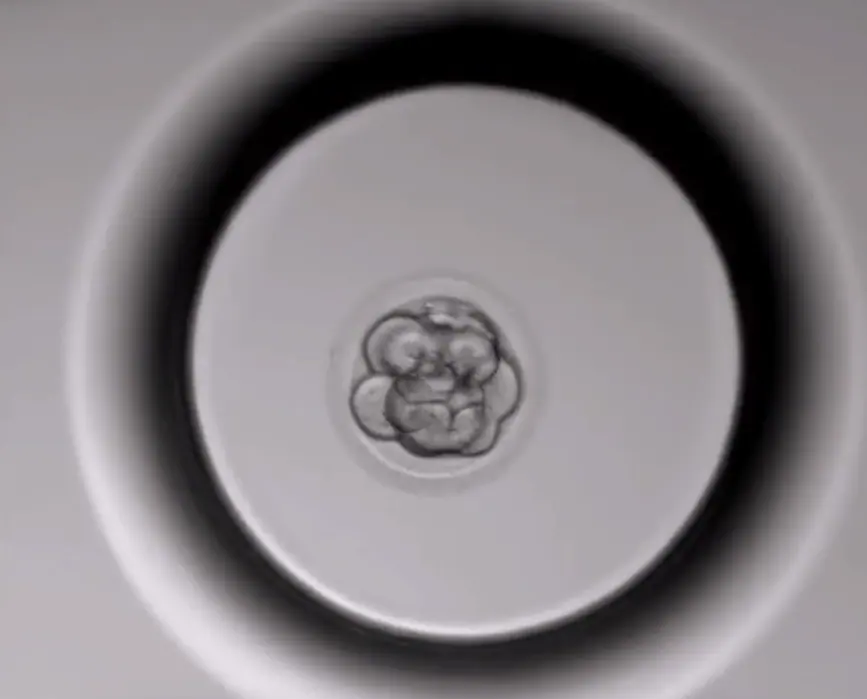

Podívejte se na vývoj embya v inkubátoru Geri

Jak může být pro embryology i pacienty užitečné? Vývoj embryí se v laboratoři běžně hodnotí jen několikrát během celé šestidenní kultivace. Proto, aby se zabránilo velkým výkyvům z optimálních podmínek pro růst a vývoj, musí být toto hodnocení rychlé a doba, kterou stráví embrya mimo inkubátor, musí být redukována na minimum. To ale znamená, že embryolog pod mikroskopem zhodnotí embryo jen na základě toho, jak vypadá v jednom konkrétním okamžiku. Pro každé embryo, které se vyvíjí v inkubátoru GERI, je každých několik minut pořízen snímek. Ze snímků vzniká průběžně video, na němž je přehledně vidět, jak se embryo během prvních dnů svého života vyvíjí. Kontinuální snímání tedy umožní embryologovi dostatečně posoudit celý vývoj a poskytuje mu dost informací, na základě kterých vybere k použití to nejvhodnější embryo.

Mezinárodní studie potvrzují, že časosběrné sledování vývoje embryí může pomoci lépe porovnat embrya, která na první pohled vypadají stejně. Taková embrya mohla vyrůst docela odlišně – jedno z nich mohlo mít rovnoměrný buněčný vývoj a druhé ne, což naznačuje jejich zcela odlišné šance na uhnízdění a budoucí těhotenství.